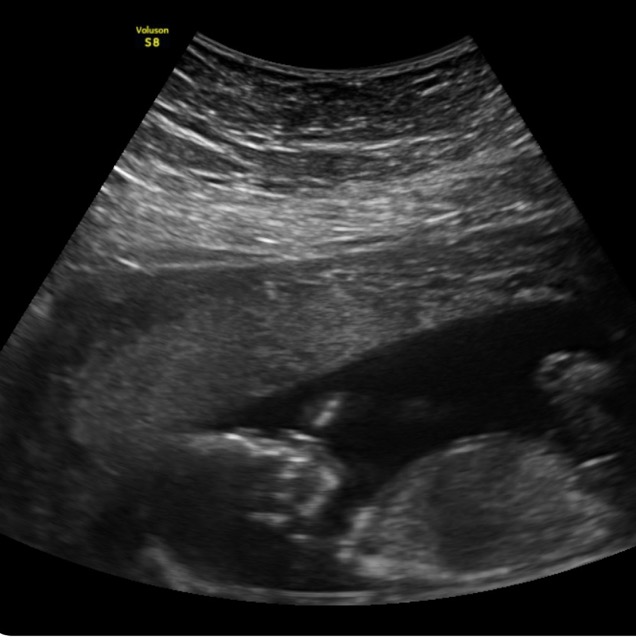

We are having a little girl this time! Baby number 2! She sucks her thumb like her brother Phoenix did in my tummy! So excited to get to experience both worlds with a little boy and a little girl! Blessed!